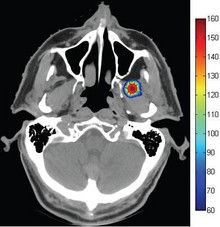

Thermal ablation in the head and neck requires accurate thermal dose delivery to target tissue while protecting the structure and function of nearby tissue and organs. In this study, we present a method that allows importing Computed Tomography (CT) scans to COMSOL, in order to model ... Read More